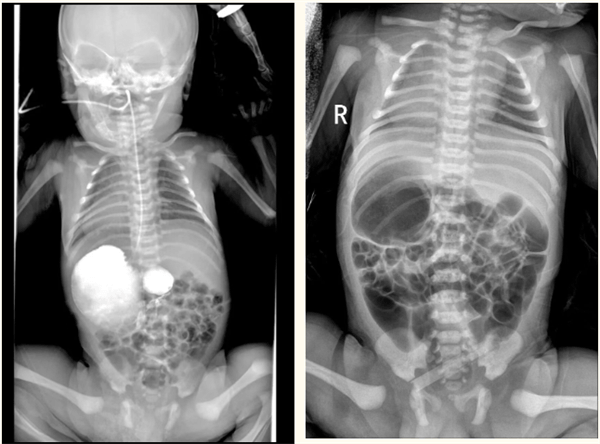

据了解,李先生夫妇的宝宝出生后便反复呕吐,这一异常情况让家人焦虑不已。经检查,宝宝被确诊为“内脏反位合并镜面右位心”——胸腔、腹腔器官位置与正常人体完全颠倒,心脏位于右侧胸腔,肝脏则在左侧腹腔,如同照镜子一般。更危急的是,检查同时发现宝宝存在十二指肠梗阻,肠内容物无法正常通过,这正是导致其频繁呕吐的根源。内脏反位本就属于少见的先天性畸形,合并肠道梗阻后,手术操作难度极大,麻醉风险也远超常规手术。

10月17日,一场关乎生命的手术正式开展。小儿外科团队在新生儿科、医学影像科、超声医学科、麻醉手术科等科室的通力配合下,小心翼翼地探查宝宝腹腔。术中发现,由于脏器位置异常,宝宝的胃腔、脾脏位于右侧,肝脏、十二指肠位于左侧,且胰腺恰好包裹住十二指肠,导致肠道梗阻,十二指肠上段已明显扩张。医生精准实施十二指肠菱形吻合术,成功解除梗阻,并留置空肠营养管以保障术后早期喂养。整个手术过程顺利,各项生命体征平稳。“先天性畸形并非‘绝症’,早发现、早干预、早治疗是关键。”市妇幼保健院小儿外科主任徐珂表示,此次“镜面宝宝”的成功救治,体现了多学科协作的成熟与高效。目前,宝宝术后恢复良好。这场跨越孕期到出生的全程守护,不仅为一个家庭带去了希望,也为面临类似情况的家庭传递了信心:面对先天性畸形,及时寻求专业医疗团队的帮助,生命便能拥有更多可能。